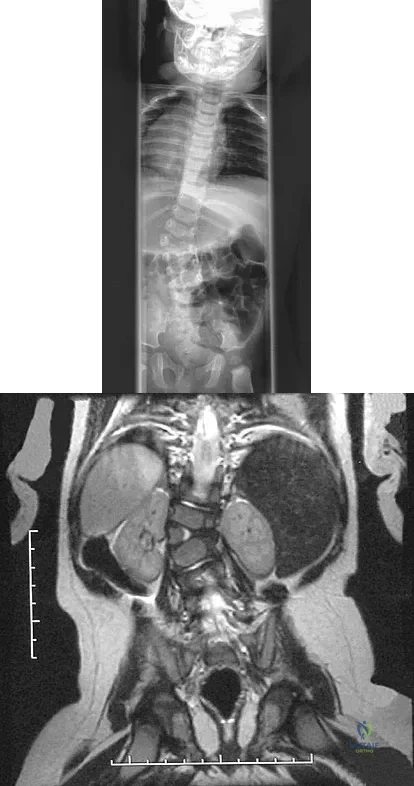

Question 31

A 2-year-old boy has complete absence of the sacrum and lower lumbar spine. What is the most likely long-term outcome if no spinal pelvic stabilization is performed?